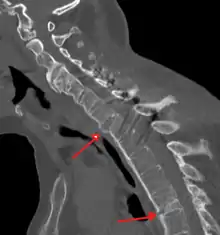

X-rays

The earliest changes demonstrable by plain X-ray shows erosions and sclerosis in sacroiliac joints. Progression of the erosions leads to widening of the joint space and bony sclerosis. X-ray spine can reveal squaring of vertebrae with bony spur formation called syndesmophyte. This causes the bamboo spine appearance. A drawback of X-ray diagnosis is the signs and symptoms of AS have usually been established as long as 7–10 years prior to X-ray-evident changes occurring on a plain film X-ray, which means a delay of as long as 10 years before adequate therapies can be introduced.[24]

CT scan showing bamboo spine in ankylosing spondylitis